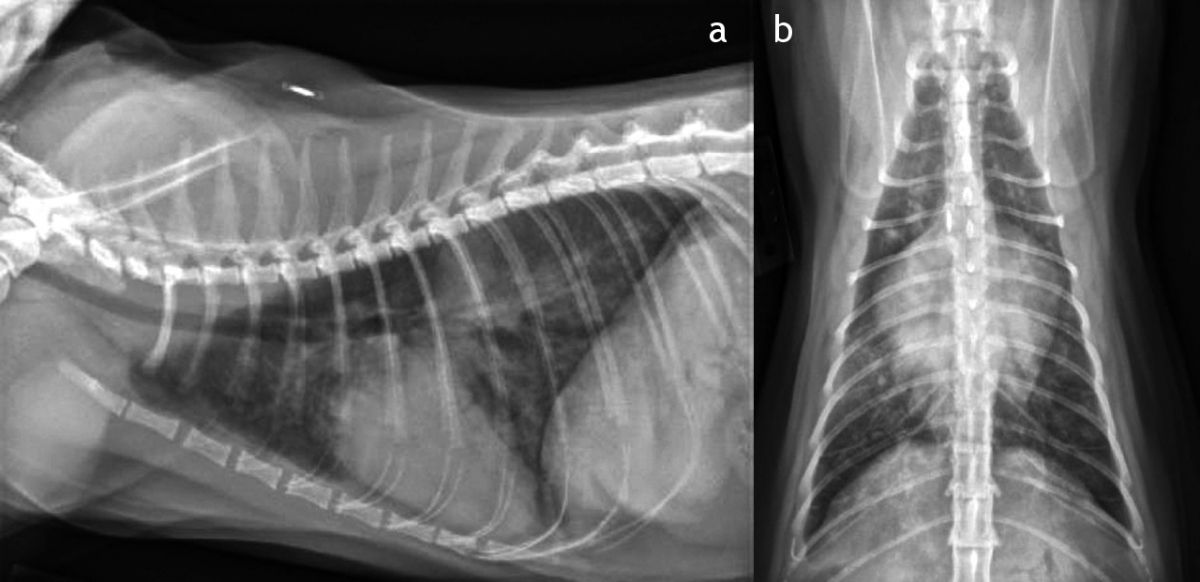

La fréquence et les efforts respiratoires seront observés lorsque le patient est calme. Malheureusement, l’auscultation des poumons n’est pas un moyen fiable pour mettre en évidence un œdème pulmonaire ou une effusion pleurale chez les chats. Par conséquent, si des signes cliniques d’ordre respiratoire sont visibles chez le chat, trois radiographies thoraciques (deux vues latérales et une ventrodorsale) seront réalisées ( Figure 1 , Figure 2 et Figure 3 ). L’abdomen sera palpé doucement pour repérer une éventuelle organomégalie ou une ascite, qui pourrait orienter vers une insuffisance cardiaque droite. De même, une congestion veineuse générale et/ou un pouls jugulaire indiquent une affection du cœur droit. Les anomalies cardiaques congénitales les plus fréquentes chez le chat sont listées dans le Tableau 1.

Figure 1. Radiographies thoraciques latérale (a) et ventrodorsale (b) normales chez un jeune chat. Trois radiographies thoraciques sous des angles différents doivent être envisagées si le patient présente des signes cliniques d’ordre respiratoire.&nbsp;© Camden Roube